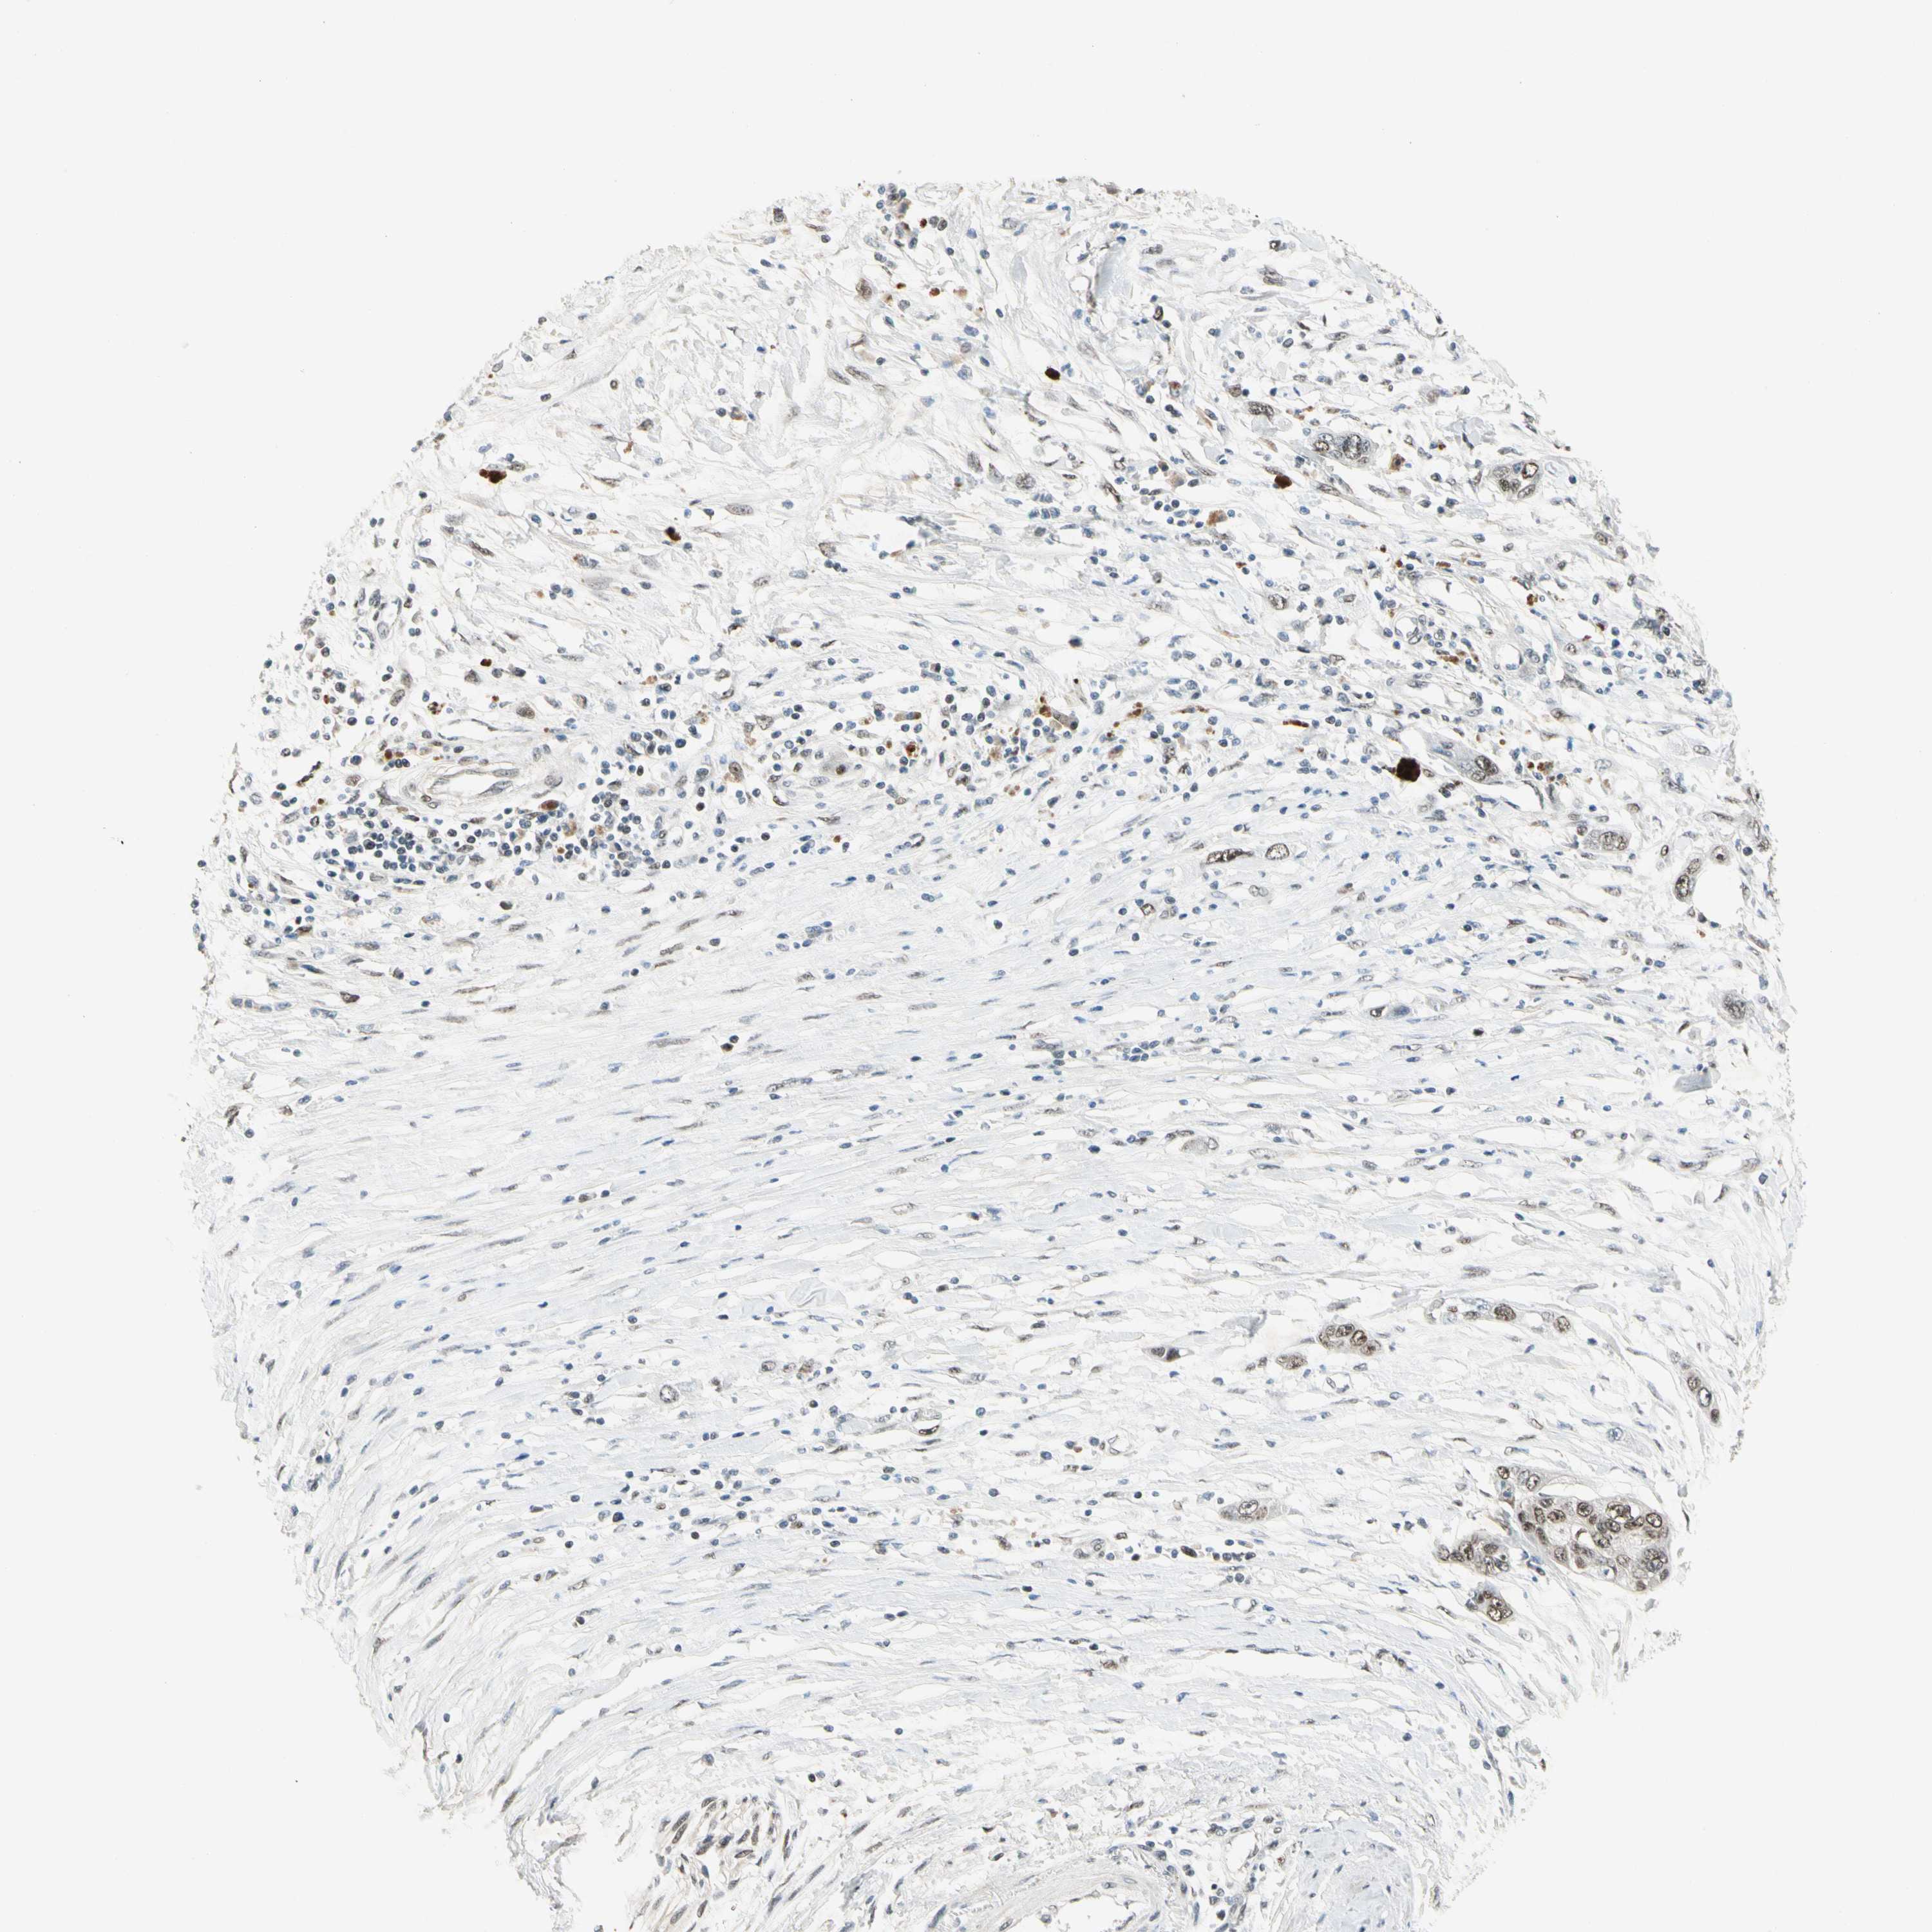

PANCREATIC CANCER - Protein expressioni

A mouse-over function shows sample information and annotation data. Click on an image to view it in a full screen mode. Samples can be filtered based on level of antibody staining by selecting one or several of the following categories: high, medium, low and not detected. The assay and annotation is described here.

Note that samples used for immunohistochemistry by the Human Protein Atlas do not correspond to samples in the TCGA dataset.

Antibody stainingi

Antibody staining in the annotated cell types in the current human tissue is reported as not detected, low, medium, or high, based on conventional immunohistochemistry profiling in selected tissues. This score is based on the combination of the staining intensity and fraction of stained cells.

Each image is clickable and will lead to virtual microscopy that enables deeper exploration of all samples and also displays staining intensity scores, fraction scores and subcellular localization as well as patient and tissue information for each sample.

Antibody HPA007990

Staining

High

Medium

Low

Not detected

Intensity

Strong

Moderate

Weak

Negative

Quantity

>75%

75%-25%

<25%

None

Location

Nuclear

Cytoplasmic/membranous

Cytoplasmic/membranous,nuclear

Adenocarcinoma, NOS